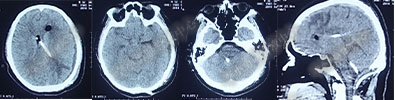

2017年6月27日(分流术后5天),复查头部CT(图-6)显示幕上脑室及第四脑室均有所缩小。

图-6:2017年6月27日头部CT

图-7:2017年7月30日头部CT

图-8:2017年9月18日头部CT